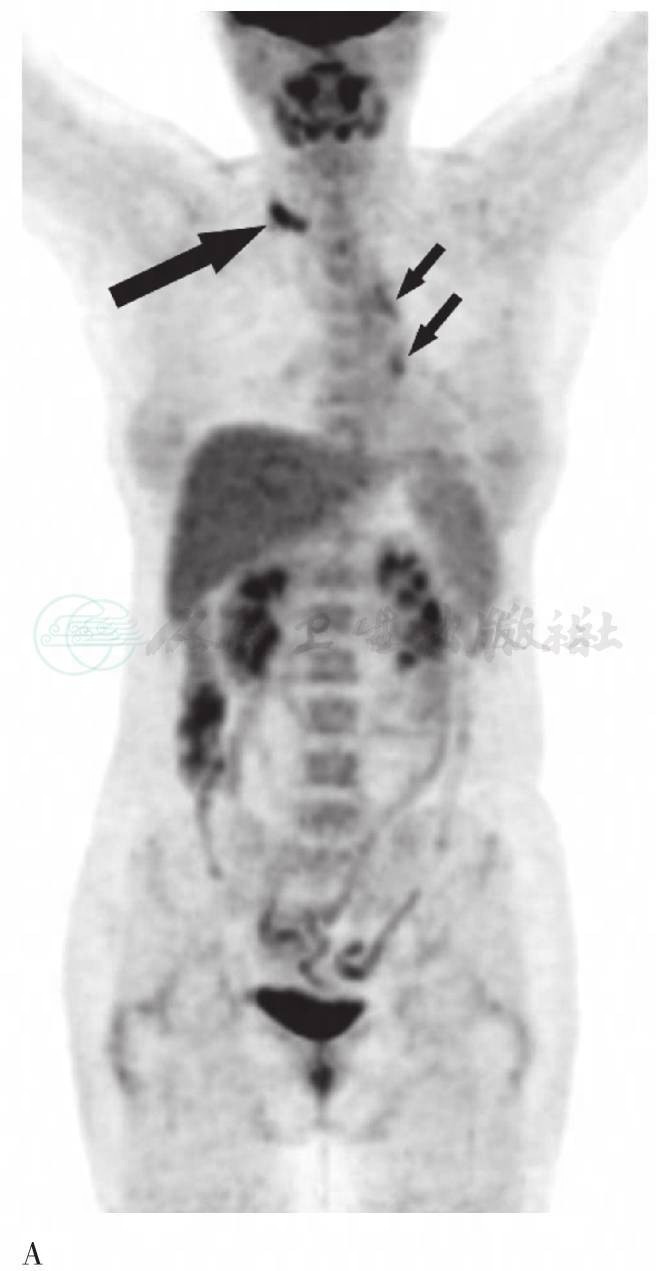

图1 (2008年10月9日)FDG PET/CT图像

A. PET MIP显像:颈部横断层图;B. CT纵隔窗;C. PET图像;D. PET/CT融合图像。右侧颈部多发淋巴结放射性摄取增高,SUVmax为5.0(长粗箭头)。CT示右上肺条索影伴多发钙化灶,肺门及纵隔内散在钙化。左肺术后改变,PET示左肺门淋巴结放射性摄取增高,SUVmax为2.6;左肺内斑片影放射性摄取轻度增高,SUVmax为2.4(短细箭头)